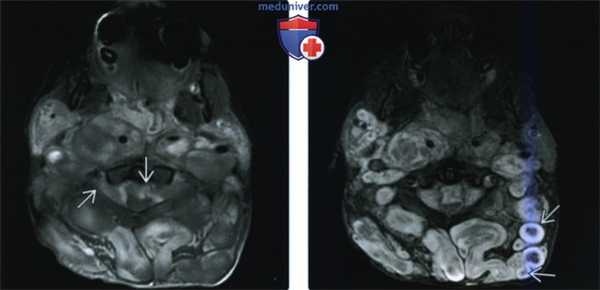

(Слева) При аксиальной МРТ Т1ВИ С+ FS у этого же пациента определяется схожая картина контрастною усиления («пятнистое» в центре и отсутствие по периферии). Обратите также внимание на распространение опухоли в позвоночный канал со сдавливанием верхних шейных сегментов спинною мозга.

(Справа) При аксиальной МРТ (STIR) все изменения становятся более выраженными. Обратите внимание, что несколько очагов имеют типичный вид «мишени» (в аксиальной плоскости), в то время как другие больше напоминают «трамвайные рельсы» (срез вдоль длинной оси).